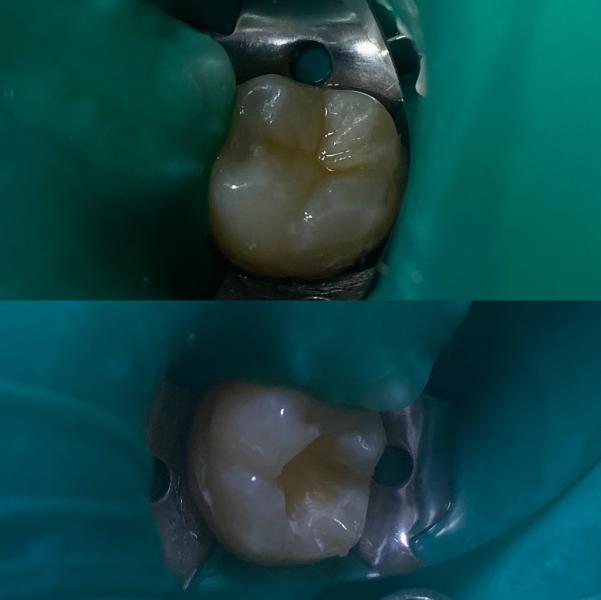

Лечение глубокого кариеса 🤍